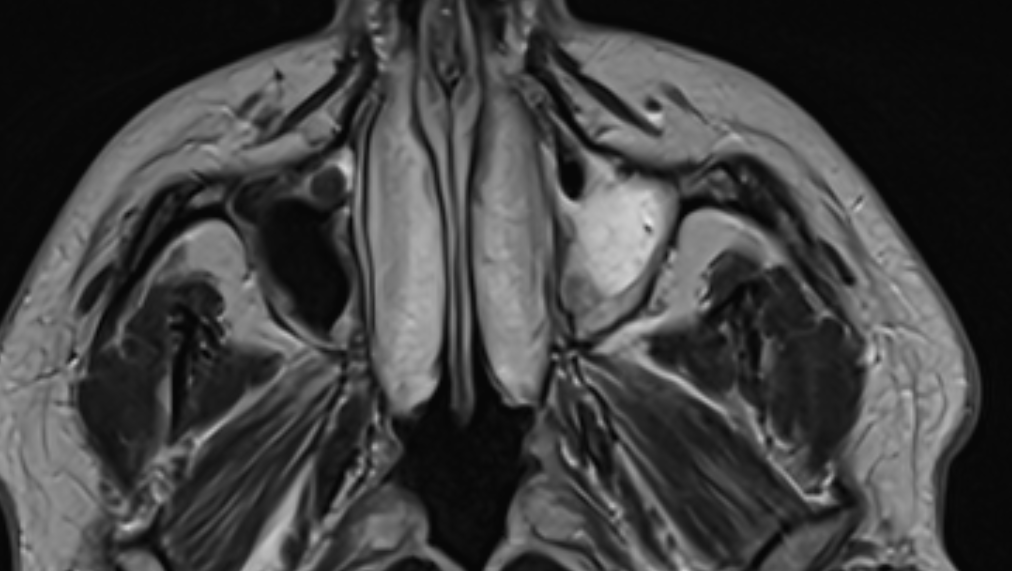

I have been experiencing constant tinnitus, head pain, inflammation & redness of my face for months now, relentlessly. Pain in my neck and spine, tingling, tremors, temperature deregulation, and muscle spasms on the left half of my body. I have had a million blood tests, multiple MRI's, and multiple CT scans, and they don't show anything conclusive despite the left side of my face being permanently red and yellow.

(The sinus cavity on the right here, my left, shows inflammation in bright white)